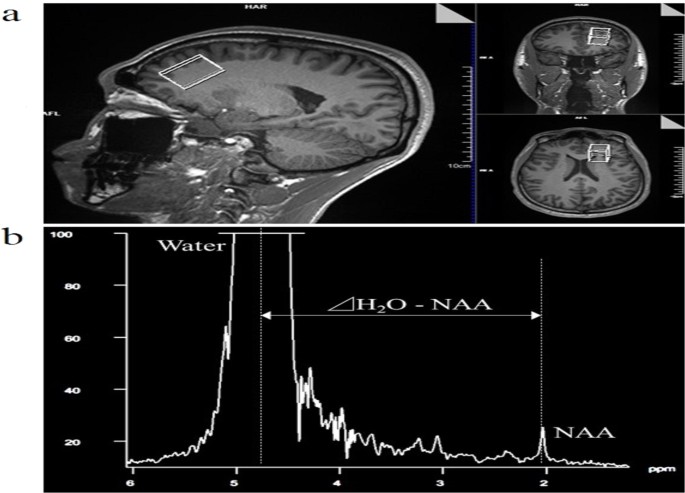

MRI and MRS were performed using a 3-Tesla MRI scanner (Magnetom Skyra; Siemens Healthcare, Erlangen, Germany) and 64-channel head/neck coil. Three-dimensional (3D) T1-weighted images (magnetisation prepared rapid acquisition with gradient echo) were acquired using the following parameters: repetition time (TR), 1,900 ms; echo time (TE), 2.29 ms; inversion time, 850 ms; flip angle (FA), 8°; matrix, 356 × 256; field of view, 240 mm; and slice thickness, 1 mm1. Hydrogen MRS was performed with point-resolved spectroscopy localisation. Acquisition parameters were as follows: TR, 10,000 ms; TE, 135 ms; FA, 90°; data size, 2048; spectral width, 1,200 Hz; and excitation, 1. The voxel of interest (VOI) was set in the frontal cortex, which has been shown to correlate with cognitive function21, using the 3D-T1 image (Fig. 1a). The VOI size was 20 × 30 × 20 mm. The magnetic resonance spectrum showed choline-containing compounds at 3.2 ppm, creatine phosphate at 3.0 ppm, and NAA at 2.0 ppm. Tbrain was calculated from the chemical shift between NAA and water using the equation (1) proposed by Cady et al.12:

where Δ was the difference between NAA and the water chemical shift (Fig. 1b). We used NAA peak because it is easy to observe and has been used in many earlier studies12,13,14,15,16,17,18.